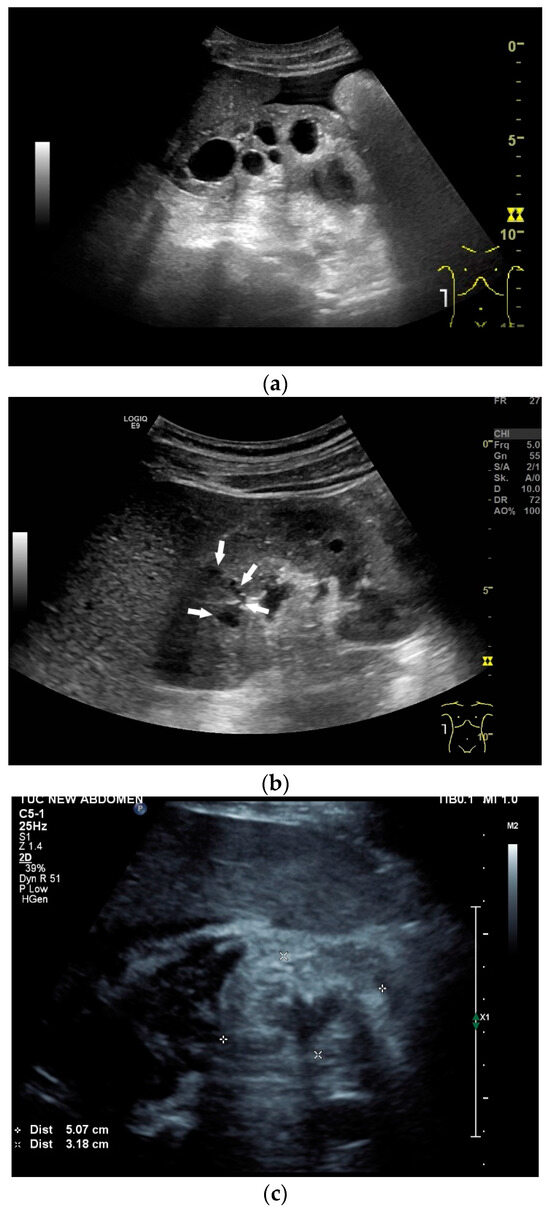

Figure 8.

Tuberculosis of the uterus and adnexae. Female patients with tuberculosis in India. Pelvis with tubo-ovarian masses: Hypoechoic lesion in right adnexa (arrows) (a) and hypoechoic lesion in left adnexa and a small amount of free fluid (arrows) (b). Free fluid in the Douglas space (arrows) (c). Thickened right fallopian tube (RT FT) (arrows) (d); thickened left fallopian tube (LT FT) (arrows) (e).